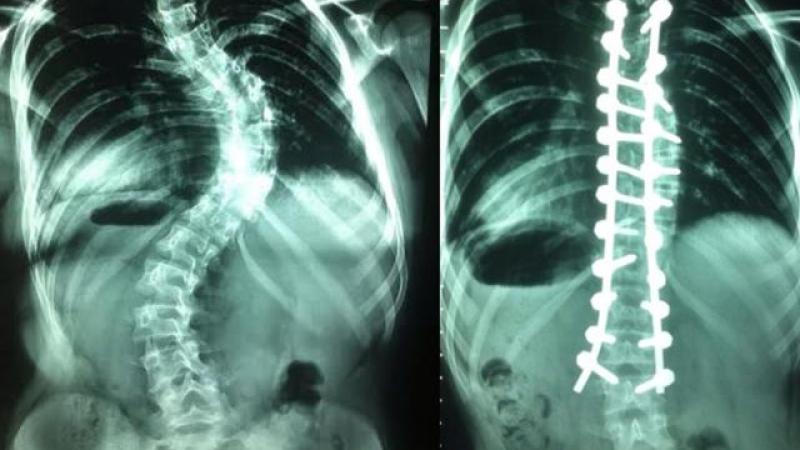

Cirugía de alta complejidad corrigió deformación de columna a niña

Una niña de 12 años presentaba una malformación de la columna, de hasta en 72 grados, el cual ponía en riesgo su vida y, por ende, su movilidad. Sin embargo, gracias a un minucioso trabajo de especialistas del Departamento de Traumatología del Hospital Guillermo Almenara de EsSalud se pudo corregir esta imperfección implantando 23 tornillos con barras de titanium.